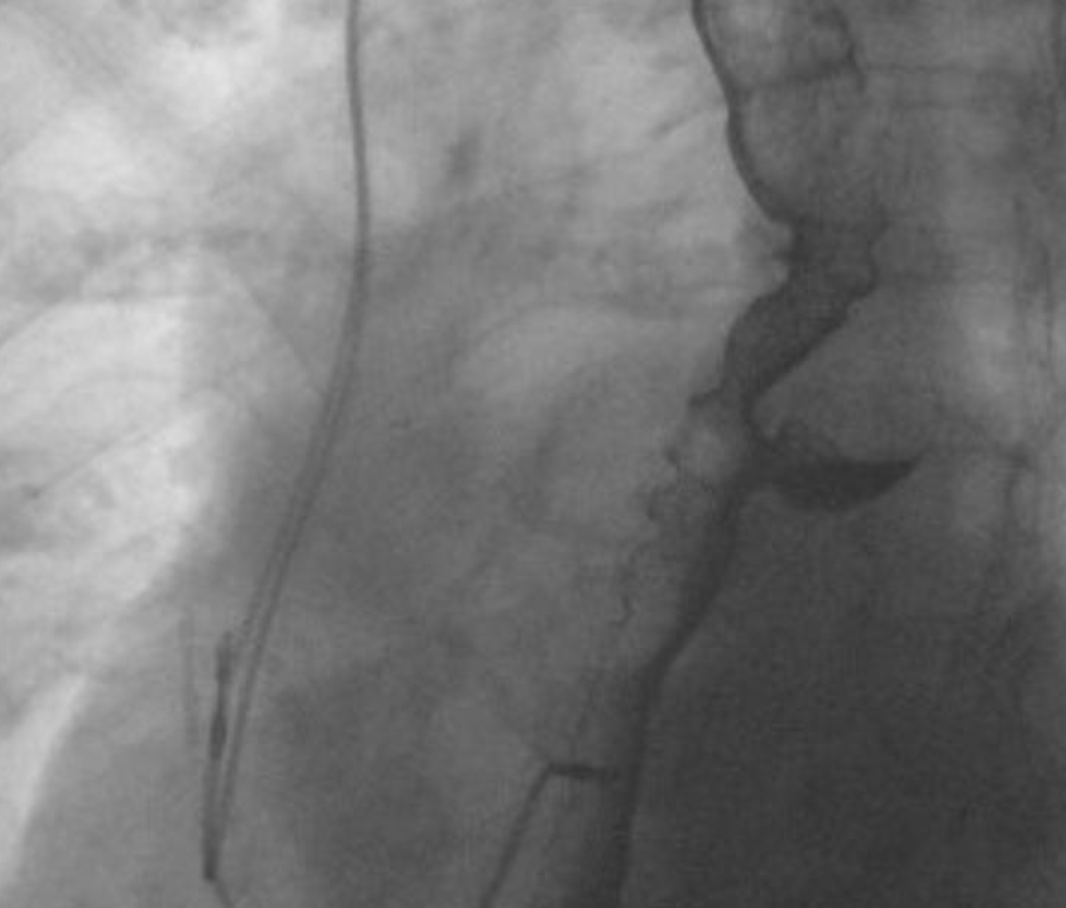

What is this?

traction diverticula: are (true diverticula) which occur secondary to scarring, fibrosis and inflammatory processes (tuberculous adenitis) in the mediastinum pulling on the oesophageal wall